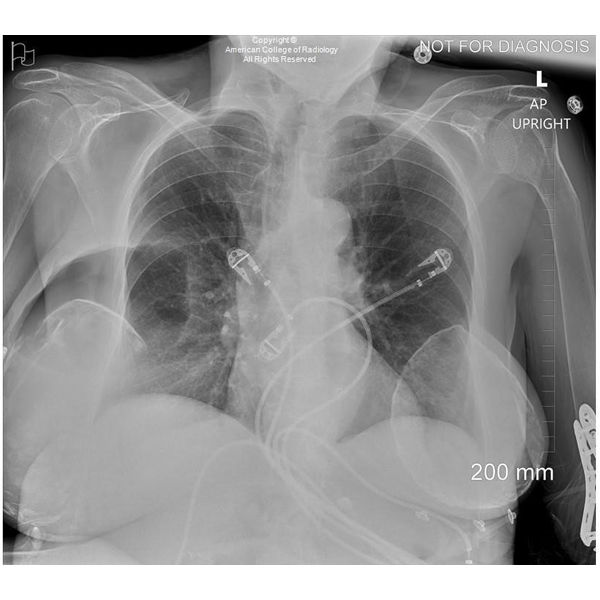

A 36-year-old female without significant medical history presents for evaluation of a rapidly enlarging left breast mass.#ACRCaseinPoint

https://t.co/gm0tueNxh4